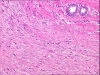

Background: Fibromatosis or desmoid tumor is a rare soft tissue tumor that lacks a metastatic potential, but is characterized by a locally aggressive and infiltrating growth pattern and a high propensity toward local recurrence if incompletely excised.

Case presentation: We report a patient with three post-surgical recurrences of fibromatosis of the breast over a seven year period. The fibromatosis was found to be involving the chest wall musculature and causing persistent and worsening pain. An aggressive operative strategy was undertaken, consisting of mastectomy with en bloc resection of the underlying chest wall musculature, ribs, and parietal pleura.